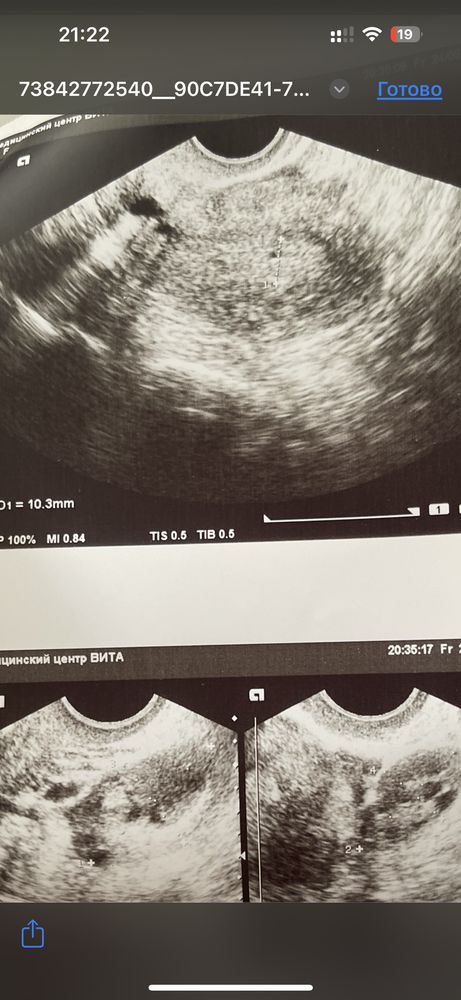

Алина А, да, почему то текст оборвался( У меня сегодня 14 ДЗ. 4 дня назад ходила на узи сказали не понятно, есть беременность или нет. Так же в тот день делала тест на беременность (но вечером) был отрицательный. Цикл у меня не стабильный, прыгает, возможно О была позже. На верхнем узи есть маленький кружок, возможно ли что это беременность или я уже что то себе напридумывала 🙈

Оля, на 14 дз уже бы тест точно показал. А плодное яицо можно увидеть минимум от 1000 хгч.